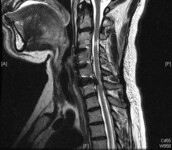

Doença degenerativa da coluna cervical

Um único nível de compressão da medula espinhal com alterações em T2, na sequência sagital cervical de T2 na presença de mielopatia cervical degenerativa sintomática

Dennis A. Turner, MA, MD